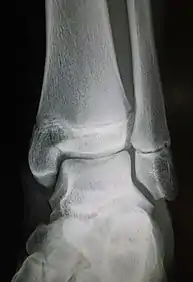

The Maisonneuve fracture is a spiral fracture of the proximal third of the fibula associated with a tear of the distal tibiofibular syndesmosis and the interosseous membrane. There is an associated fracture of the medial malleolus or rupture of the deep deltoid ligament of the ankle. This type of injury can be difficult to detect.[1][2]

Ankle radiographs are used to detect widening of the tibiofibular syndesmosis or medial clear space. The medial clear space is the area between the talus of the ankle and the medial malleolus. Damage to the deltoid ligament and syndesmotic ligaments result in mortise instability, causing the talus to laterally shift and widen the medial clear space.[4][12] A clinical study, conducted in 2006 and published in the Journal of Bone and Joint Surgery, found that the medial clear space size of a normal ankle and an injured ankle measured at 4 millimetres and 5.4 millimetres in length respectively.[11] To confirm diagnosis, full-leg radiographs are used to inspect for fractures of the proximal fibula and widening of the interosseous clear space (or tibiofibular clear space). The interosseous clear space is the area between the medial side of the fibula and lateral side of the tibia. A peer-reviewed study, published in Injury in 2004, found that an interosseous clear space greater than 10 millimetres indicates diastasis of the syndesmotic ligaments.[4]